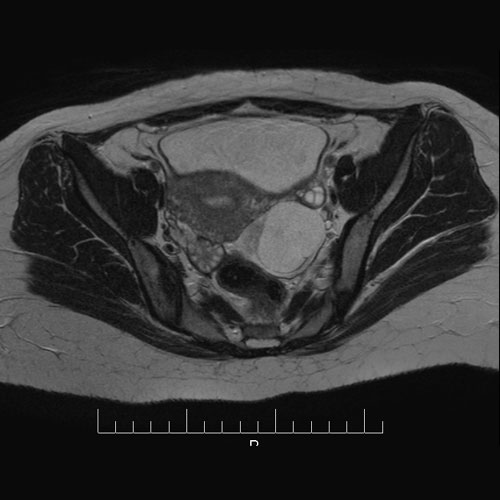

28 year old female with left lower abdomen pain. MRI showing torsion of Fallopian tube.